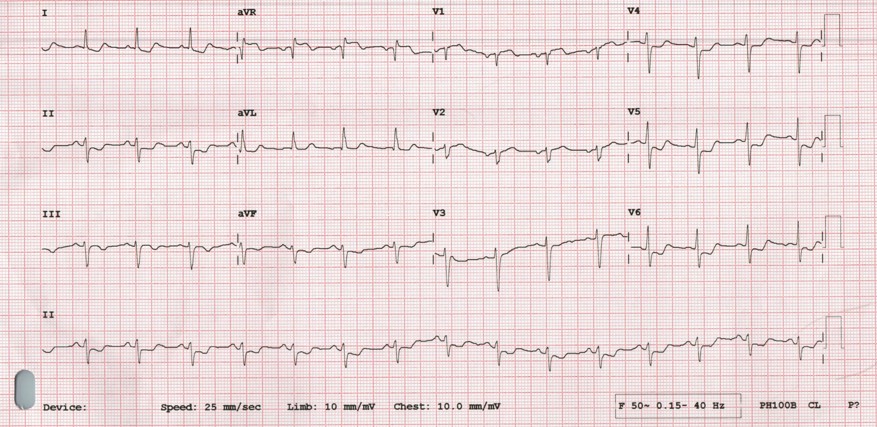

Initial electrocardiogram demonstrated diffuse ST-segment depression with ST-elevation in leads aVR and V1. The patient subsequently developed ventricular fibrillation requiring immediate cardiopulmonary resuscitation and defibrillation. During emergency transfer to the cardiac catheterization laboratory, she experienced recurrent ventricular fibrillation and profound cardiogenic shock.